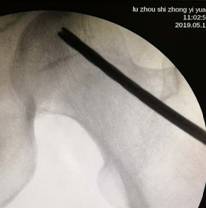

術(shù)中,為患者打通“隧道”,注入血小板

經(jīng)過術(shù)前與麻師團隊詳盡的討論及預(yù)案制定后,手術(shù)醫(yī)師首先為吳先生實施雙側(cè)股骨頭壞死髓芯減壓,即打開一個像筷子大小的“隧道”孔后,再通過“隧道”將分離的血小板注射進吳先生骨頭壞死區(qū)域。整個手術(shù)僅抽取了80毫升血液,耗時數(shù)十分鐘,術(shù)后三天患者出院。